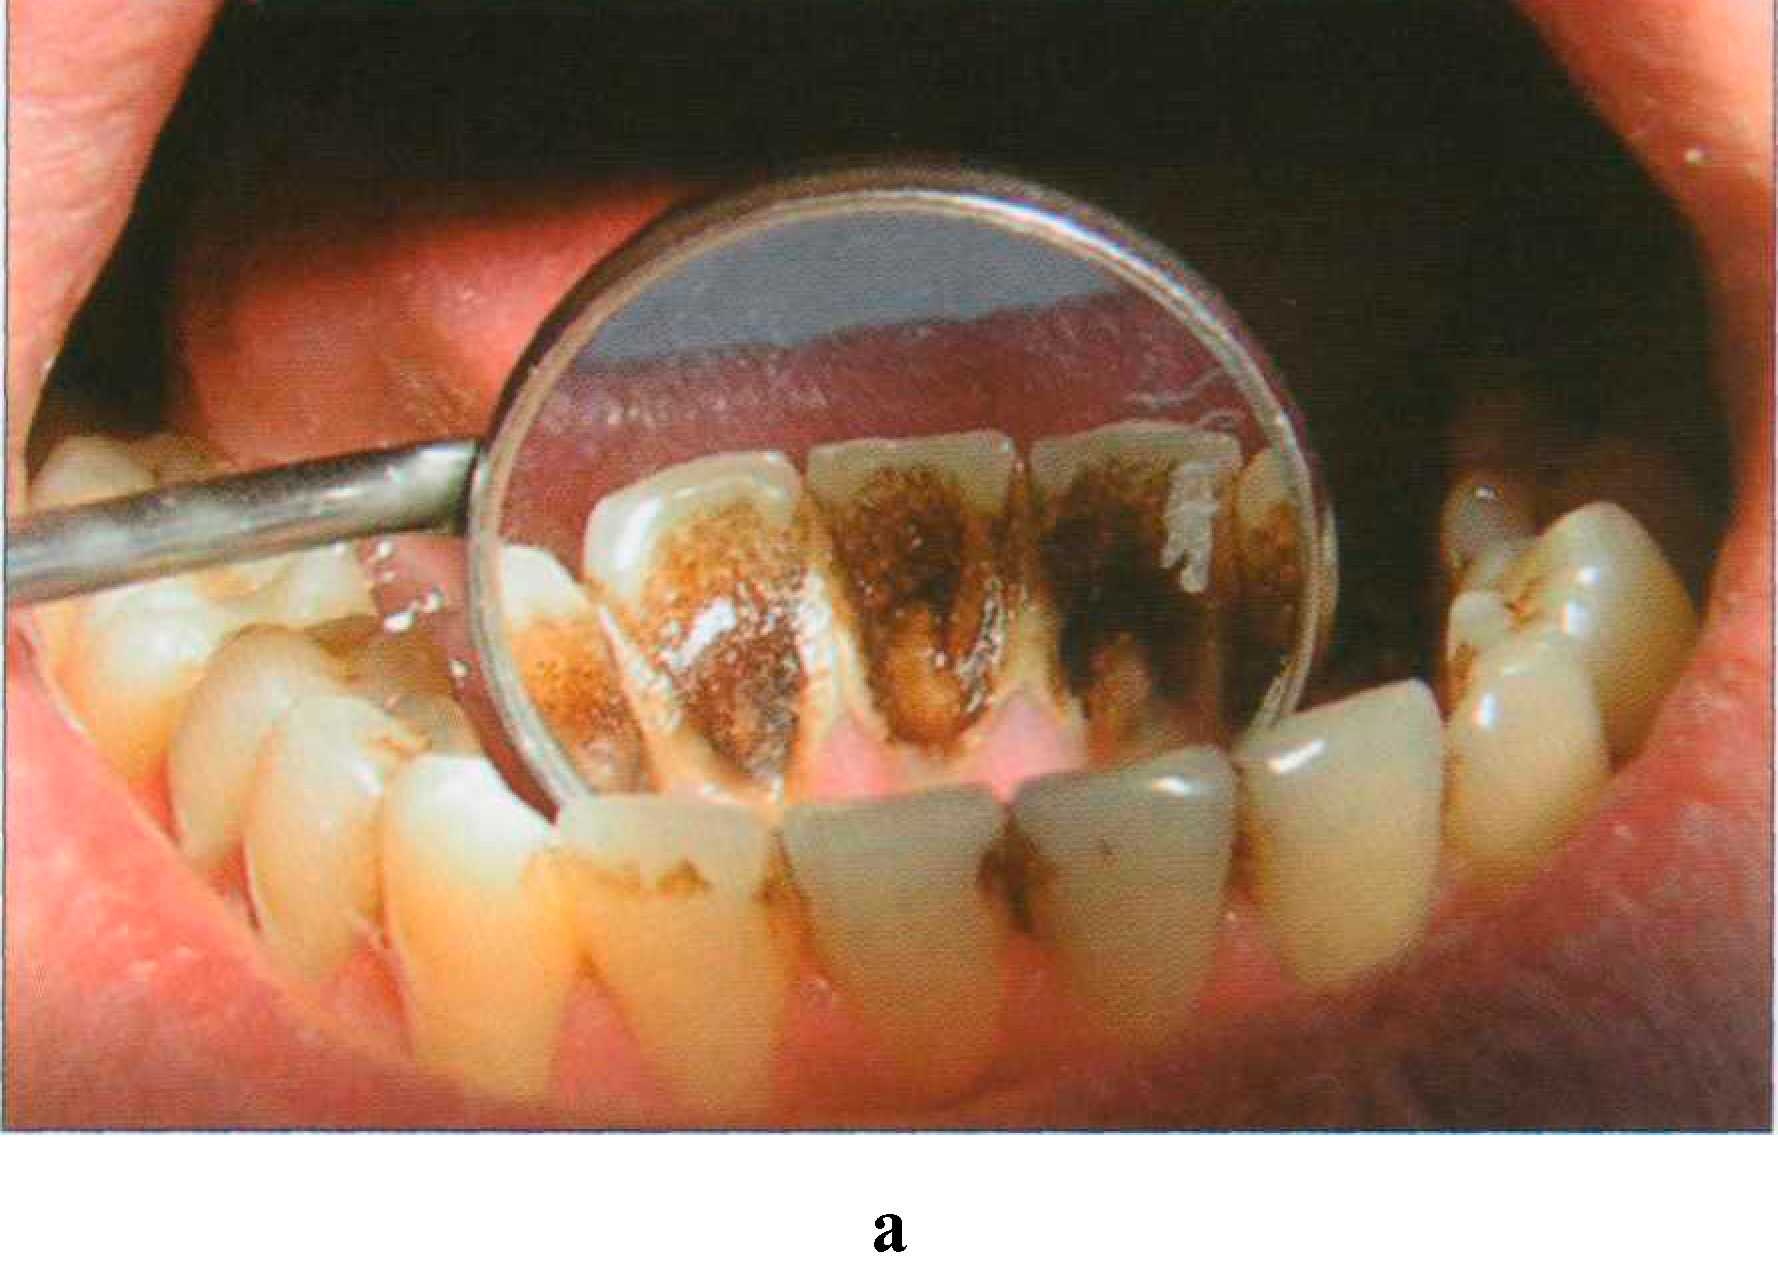

Благодаря высокой пористости участки деминерализации могут пигментироваться, приобретая желтоватую, бурую, коричневую окраску в зависимости от воздействующего красителя. Пары брома и йода окрашивают пришеечные области зубов в желтоватый цвет. Коричнево-черный налет на зубах появляется у лиц, занятых обработкой металлов (марганец, железо, никель). Хроническое отравление ртутью, сулемой, свинцом приводит к диффузному окрашиванию зубов различной интенсивности от серого до черного или от желтого до коричневого цвета. Особо следует остановиться на пигментации зубов у курильщиков (экзогенное, системное, поверхностное и глубокое окрашивание). Наиболее характерно образование темно-коричневого, почти черного налета вдоль шеек зубов, а также на тех поверхностях, которые не участвуют в жевании и плохо очищаются. Образованию «налета курильщиков» способствует плохая гигиена полости рта (рис. 173 а, б).

Рис. 173. Выраженная пигментация язычной поверхности резцов: налет "курильщика" — а; состояние после профессиональной гигиены — 6 Сходная окраска, которую можно отнести к воздействию пищевых пигментов, однако менее интенсивная и менее стойкая, чем у курильщиков, наблюдается у любителей крепкого чая и кофе. Содержание в питьевой воде железа может вызвать устойчивую синеватую окраску зубов. Выраженная пигментация органических покровов зуба может появляться в результате воздействия хлоргексидина, который назначают для полосканий (рис. 174).